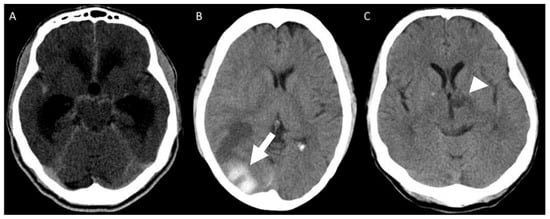

Mean CSF cell count at first lumbar puncture was 71.5/mm3 (range 3–363/mm3) with lymphocytic predominance in all but one patient, protein level of 117.9 mg/dL (range 33–307 mg/dL), and glucose level of 39.6 mg/dL (range 16–65 mg/dL). In 11/17 (64.7%) patients, Sporothrix spp. was identified in the CSF: isolated from CSF culture in seven (41.2%) patients, and a positive PCR for the fungus was present in other four (23.5%) patients, as previously described []. Sporothrix brasiliensis was the identified species in all the available isolates from any clinical specimen of 11 (64.7%) patients, including five CSF isolates. All patients underwent brain CT scans or MRI. Meningeal contrast enhancement or hydrocephalus were each present in 9 (52.9%) patients (Figure 3A). One patient had a hemorrhagic stroke (Figure 3B), and ischemic lesions were present in two (Figure 3C). In 5 (29.4%) patients, imaging studies disclosed no abnormalities.

Figure 3.

Brain CT scan showing (A) ventricular dilatation and basal cisterns contrast enhancement; (B) a parieto-occipital hemorrhagic lesion (white arrow) and (C) left thalamic ischemic lesion (white arrowhead).

Imaging findings are nonspecific and may be absent in some patients. Contrast enhancement of cerebral sulci and the basal cistern is highly suggestive of leptomeningitis, but it is not present in all cases. Blocking of CSF circulation led to ventricular dilatation in half of the patients and may be life-threatening, requiring ventricular shunting. Vascular lesions have been described previously in patients with meningeal sporotrichosis [,]. Donabedian et al. observed thrombotic endarteritis of small- and medium-sized brain vessels leading to multiple infarcts suggesting an inflammatory mechanism [].